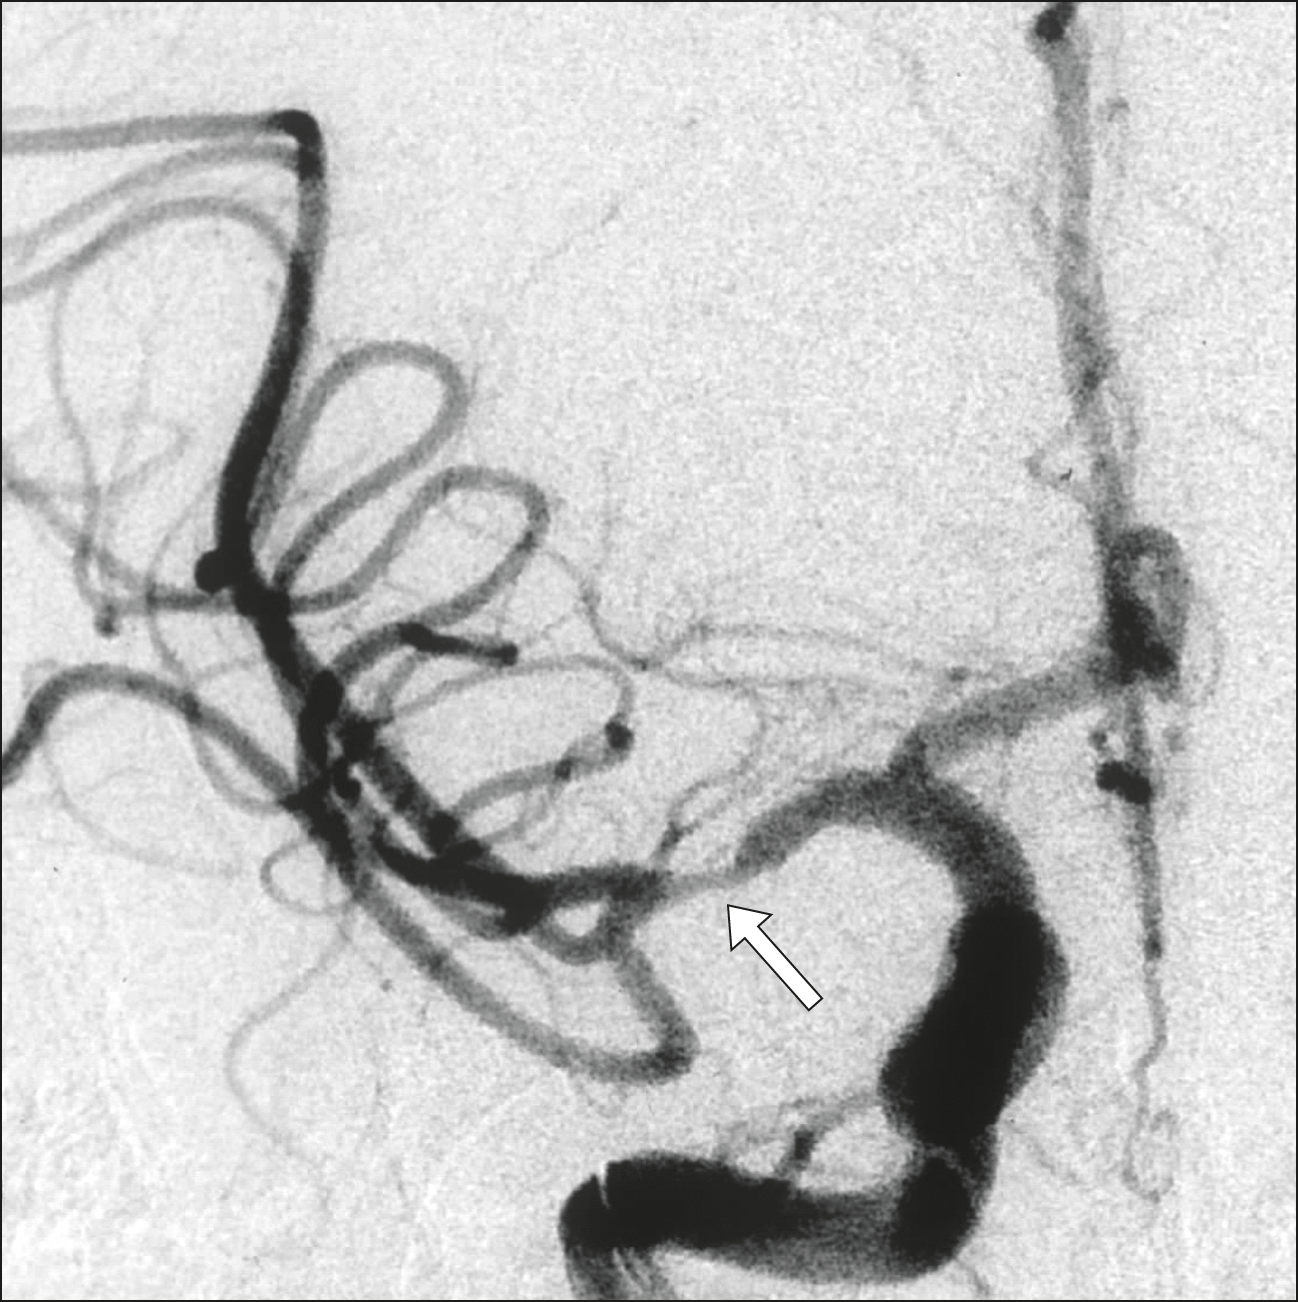

Terapia endovascular del ACV: cómo son los resultados en la vida real

El registro nacional holandés de las intervenciones para el tratamiento inicial del ACV isquémico muestra resultados comparables a los obtenidos en los ensayos clínicos. BMJ, marzo de 2018